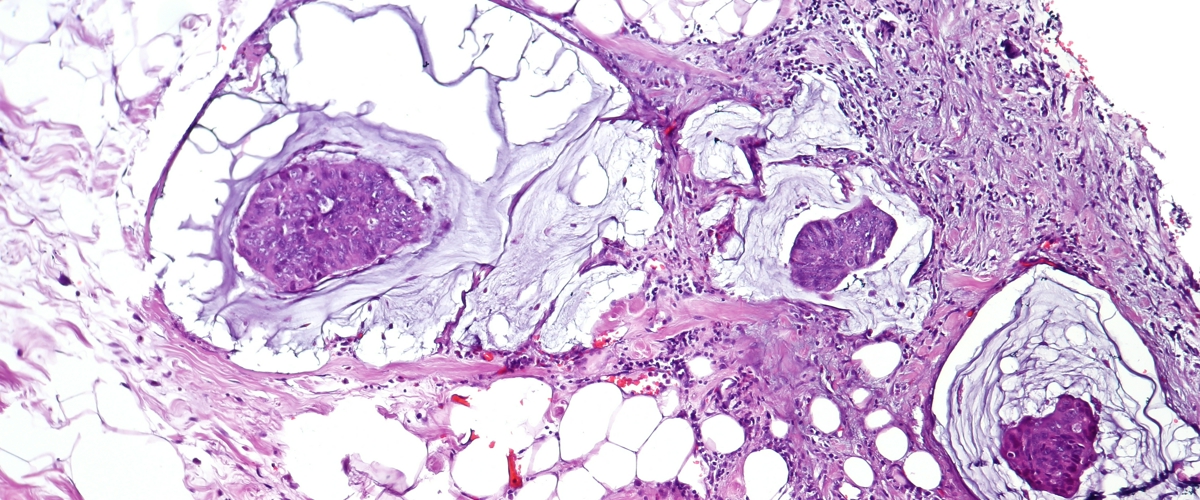

Колоноскопия — золотой стандарт в диагностике рака кишечника, но далеко не идеальный. Представьте: врач внимательно осматривает слизистую через камеру, берет образцы... и все равно может пропустить крошечную, но коварную опухоль на ранней стадии. А уж заглянуть в глубокие слои ткани и вовсе не получается. Знакомая проблема, не так ли? Именно это и подтолкнуло ученых искать способы «прокачать» старый добрый метод.

В чем суть? ОКТ улавливает, как свет преломляется в тканях. Оказалось, что здоровые и пораженные клетки делают это по-разному, и эта разница видна на глубине в несколько миллиметров. Получается своего рода «рентгеновское зрение» для слизистой оболочки кишечника, которое может уловить самые первые, предраковые изменения.

Анализ этих высокоточных снимков доверили специально обученной системе. После тренировки на 26 тысячах изображений — как здоровых, так и больных тканей — она научилась ставить диагноз с пугающей, почти фантастической точностью в 100%. И всего за четыре секунды.